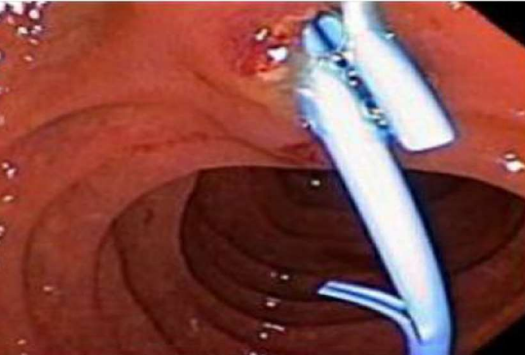

Figure 3 showing the stent eroding through the duodenum

A 23-year-old Albanian woman presented with two days of severe, intermittent epigastric and right upper quadrant abdominal pain. The pain had been ongoing over the past year but worsened two weeks prior to admission. She admitted to dark urine and light-colored stools but denied diarrhea, constipation, blood in the stool, fevers, chills, night sweats, or weight loss. She was afebrile, normotensive with a normal heart and respiratory rate. She was noted to be in moderate distress and ill-appearing with scleral icterus. Abdominal examination revealed mild epigastric tenderness without guarding or rebound. Complete blood count was within normal limits with a normal platelet count as well as a normal INR and prothrombin time. Liver panel demonstrated a total bilirubin of 4.5mg/dL, direct bilirubin of 2.8mg/dL, alanine aminotransferase 354mg/dL, aspartate aminotransferase 174mg/dL, and alkaline phosphatase 118mg/dL. Hepatitis serologies were negative. Her CA 19-9 level was elevated to 143U/ml. Abdominal ultrasound revealed multiple gallstones within the dependent portion of a normal gallbladder, the largest measuring 0.6cm, and a prominent distal common bile duct (CBD) within the pancreatic head. Magnetic resonance cholangiopancreatography (MRCP) revealed beading of the intrahepatic biliary tree with high grade strictures of the right and left hepatic ducts, suggestive of Primary Sclerosing Cholangitis (PSC), cholelithiasis, and a small stone in the distal CBD with mild dilatation of the CBD and the intrahepatic biliary ducts [figure 1A and 1B]. She underwent ERCP where brushings were obtained from the strictured portions and sent for cytology. Additionally, a sphincterotomy was performed and stones and sludge were extracted from the bile ducts. A 7Fr x 9cm straight plastic stent was placed into the right intrahepatic system and a 7Fr x 15cm straight plastic stent was placed into the left intrahepatic system, [figure 2] though this stent was seen extending slightly within the duodenal lumen. The evening after the procedure, the patient developed an episode of vomiting and abdominal pain however her physical examination appeared stable from prior examinations. Labs obtained at that time revealed mildly elevated lipase with a mild leukocytosis so her symptoms were attributed to post-ERCP pancreatitis and she was made nil per os (NPO) and treated with intravenous fluids and analgesia. Her nausea and epigastric pain subsided by the next morning but she subsequently developed right lower quadrant abdominal pain. She was scheduled to undergo laparoscopic cholecystectomy the following day so the decision was made to also perform laparoscopic evaluation for the right lower quadrant pain and possible acute appendicitis, during the procedure. The laparoscopy revealed significant bilious fluid in the right paracolic gutter associated with inflammation. Upon further evaluation, the biliary stent was noted to be eroding through the duodenum at the junction of the second and the third portions [figure 3]. The duodenal perforation was repaired and reinforced with a Graham patch. Due to the extensive inflammation, a right hemicolectomy with ileocolic anastomosis was performed with copious lavage of the peritoneal cavity. The patient did well postoperatively and was discharged on the sixth postoperative day. Cytology from the biliary stricture brushings demonstrated reactive cells without evidence of malignant cells. Pathology from the surgical specimens demonstrated a segment of small and large intestine with marked acute and chronic inflammation involving peri-intestinal fat, with abscess, hemorrhage, fat necrosis and fibrinopurulent serosal exudates. The margins of the resection appeared viable.